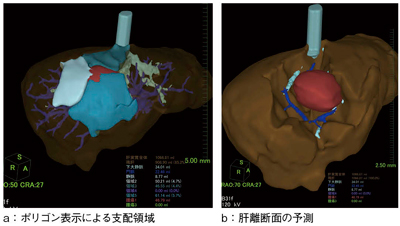

(2) ポリゴン表示:肝臓や血管モデルがシンプル(なめらか)表示になった(図3)。

図3 “新・肝臓解析”を用いた術前シミュレーション